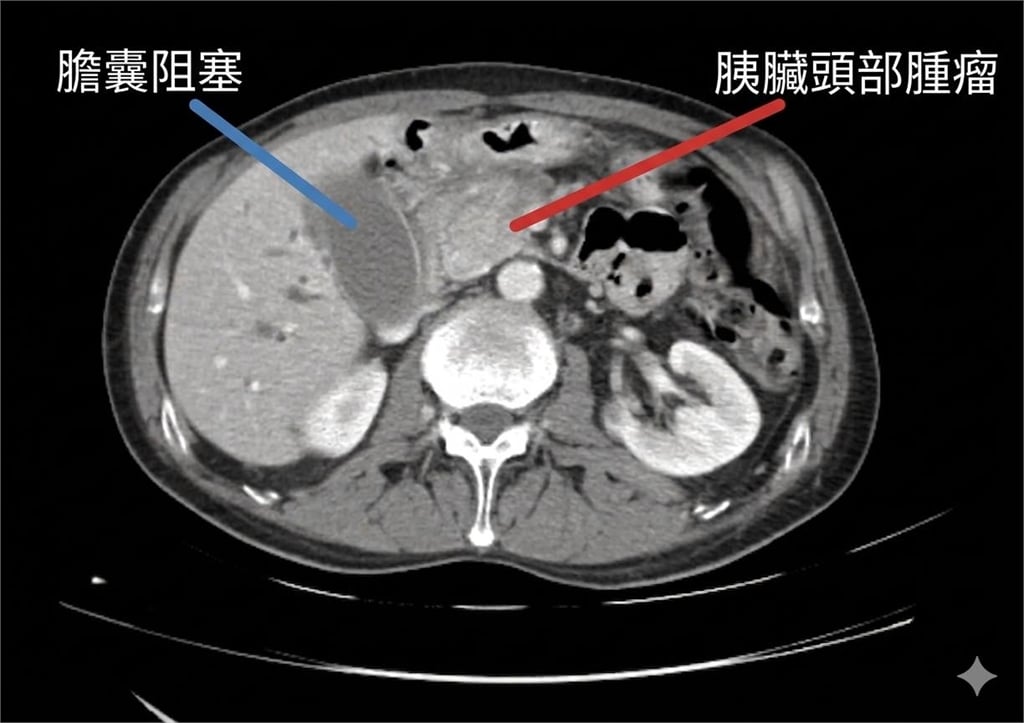

林相宏在臉書粉專分享案例,指出該名女子就診時,已出現眼白與全身皮膚泛黃的典型黃疸症狀,檢查發現黃疸指數與肝功能數值均飆高至正常值的10倍以上。進一步透過影像檢查確認,胰臟頭部已有約4公分腫瘤,確診為胰臟癌,目前正評估是否能手術治療。林相宏指出,約7成胰臟癌患者在早期幾乎無明顯症狀,若腫瘤剛好長在胰臟頭部,才可能因壓迫膽管導致膽汁無法排出,進而出現黃疸。